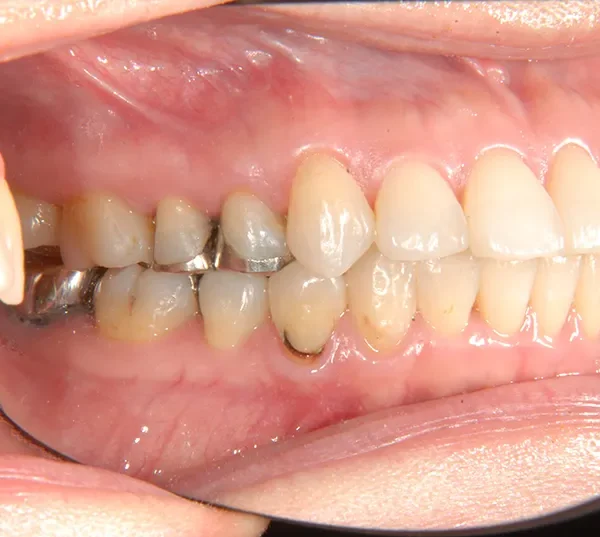

初診時年齢 40歳以上 (女性) 主訴 上下のがたがた・噛み合わない

診断名 叢生 装置名

上下のがたがたと噛み合わない事を主訴に来院されました。

歯は抜かずに矯正治療しました。

治療回数35回、2年8ヶ月の治療期間で矯正治療を終了しました。

噛み合わせが安定する事で、大きくなっていた咬筋が正常な大きさになり、顎のラインもシャープになり大変よろこばれていました。